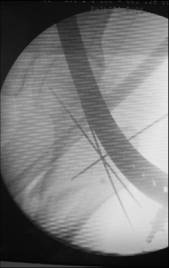

I would use a small wire distractor mentioned in the list some times. Proximal wire is in the iliac crest in AP direction. The leg is adducted. I attached some images. At the AP view under image intensifier you can see adduction but even slight valgus reduction.